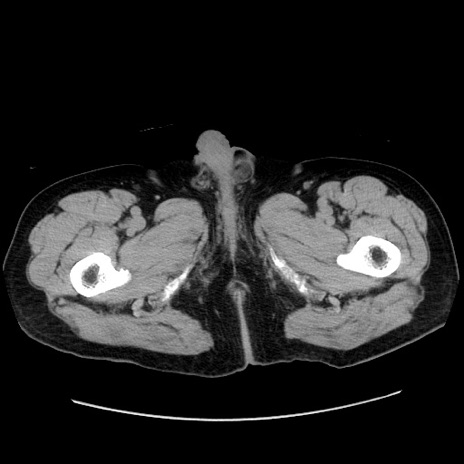

症例30(横断像)

【症例】80歳代男性

【主訴】臍周囲痛

【現病歴】約6時間前から臍下部痛が出現。次第に腹部膨隆・背部痛も生じてきたため来院。背部痛の場所は変化しない。

【身体所見】意識清明、BT 36.3℃、BP  131/87mmHg、P 87bpm、SpO2 100%(RA)、臍周囲自発痛・圧痛あり、反跳痛なし、自発痛部位に一致して板状硬あり、腹部膨隆、腸雑音減弱、CVA tenderness両側陰性。